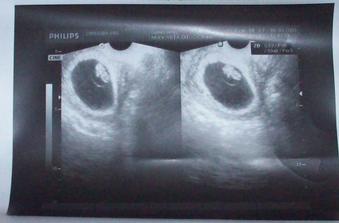

Šťastie sa na nás usmialo po 2krát🙂))))

vytúžené dve čiaročky sme našli na teste 4.februára,týžden po meškaní mršky🙂))13.2 ideme na prvú poradňu,tak dúfame,že naše miminko sa má dobre a rastie 🙂))))))))